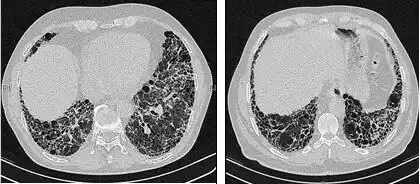

A avaliação radiológica por meio da TCAR é um ponto essencial no caminho do diagnóstico da FPI. A TCAR é realizada usando um scanner tomográfico axial computadorizado convencional sem injeção de agentes de contraste. As fatias de avaliação são muito finas, de 1 a 2 mm.

A TCAR típica do tórax da FPI demonstra alterações fibróticas em ambos os pulmões, com predileção pelas bases e pela periferia. De acordo com as diretrizes conjuntas das ATS, ERS, JRS e ALAT de 2011, a TCAR é um componente essencial da via diagnóstica na FPI, que pode identificar a PIU pela presença de:[3]

- Opacidades reticulares, geralmente associadas a bronquiectasias de tração

- Favos de mel manifestados como espaços aéreos císticos agrupados, geralmente de diâmetros comparáveis (3-10 mm), mas ocasionalmente grandes. Geralmente são subpleurais e caracterizados por paredes bem definidas e dispostos em pelo menos duas linhas. Em geral, uma linha de cistos não é suficiente para definir os favos de mel.

- Opacidades de vidro fosco são comuns, mas menos extensas do que a reticulação.

- Distribuição caracteristicamente basal e periférica, embora muitas vezes irregular.

Tomografia computadorizada de alta resolução do tórax de um paciente com FPI. As principais características são um padrão periférico, predominantemente basal, de reticulação grosseira com favos de mel